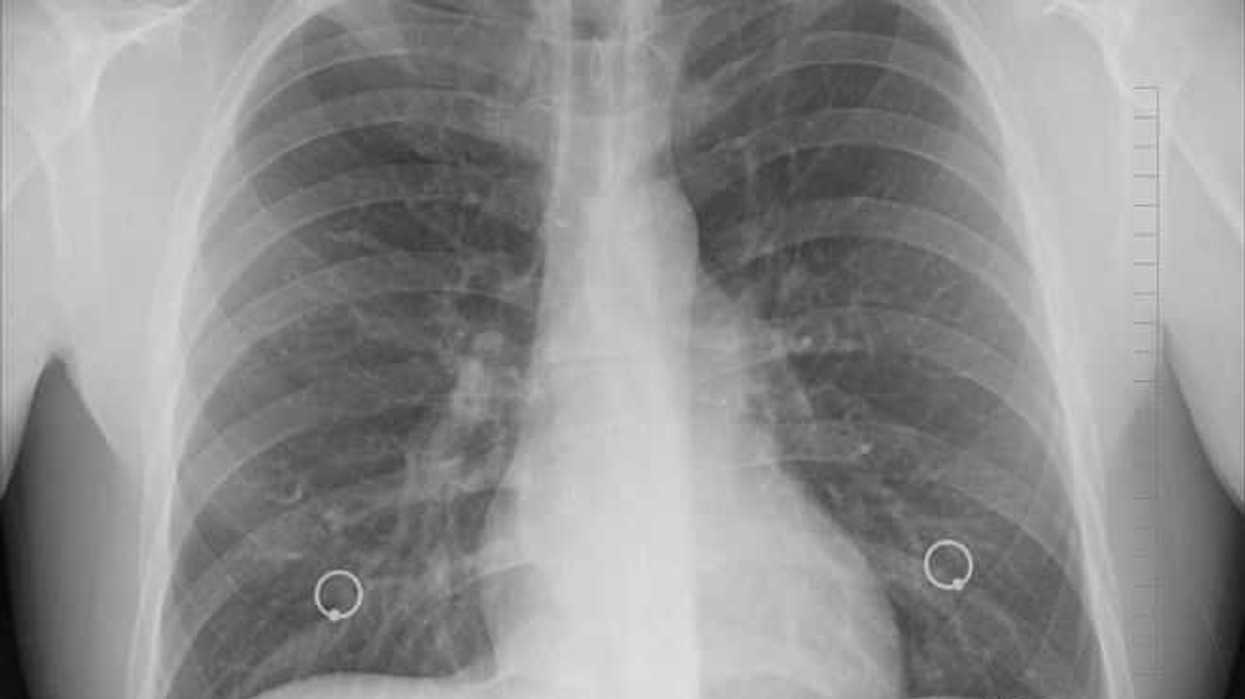

México, 7 Nov (Notimex).- En México, se detectan siete mil casos nuevos de cáncer de pulmón al año y se estima que 21 personas fallecen diario por esta enfermedad, informaron expertos en el marco del Congreso de la Sociedad Mexicana de Oncología.

Los especialistas reunidos en Mérida, Yucatán, coincidieron en la importancia de diagnosticar este padecimiento de manera oportuna, ya que en la actualidad, 95 por ciento de los casos se identifican en etapas avanzadas.